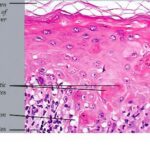

Histopathology. EM is considered the prototype of the vacuolar form of interface dermatitis . The early changes include vacuolization of the basal cell layer; tagging of lymphocytes along the dermal-epidermal junction; and a sparse, superficial, perivascular lymphoid infiltrate . Necrosis of individual keratinocytes in the basal unit occurs, which is the hallmark of EM. Because of its acute nature, there is an orthokeratotic stratum corneum. Mild spongiosis, papillary dermal edema, and extravasation of red blood cells are seen. As the lesion becomes more developed, there is a moderate lichenoid infiltrate of Iymphohistiocytes at the dermal-epidermal junction with exocytosis. More apoptotic keratinocytes within and above the basal epidermal layer are present. The |

intensity of epidermal necrosis varies from vacuolated individual keratinocytes surrounded by lymphocytes (satellite cell necrosis) at the basal unit to confluent necrosis in association with intraepidermal and subepidermal vesicles. The dermal infiltrate comprises lymphocytes and histiocytes. Eosinophils may also be present. Although one study has noted a significant number of eosinophils in drug-induced EM, this has not been noted by others. In the authors’ estimation, a generous number of eosinophils exclude EM. One study has found that an acrosyringium concentration of apoptotic keratinocytes in EM is a clue to a drug etiology . In early lesions of SJSITEN, apoptotic keratinocytes are observed scattered in the basal layer of the epidermis. In established lesions, there are numerous necrotic keratinocytes, even full-thickness epidermal necrosis, and a subepidermal bulla. The dermal inflammatory infiltrate is sparser in TEN than in EM (Fig. 9-278). Extravasated erythrocytes are commonly found within the blister cavity. Melanophages within the papillary dermis occur in late lesions. Eccrine epithelium shows a variety of changes from basal cell apoptosis to necrosis of the duct. |

In general, EM shows less epidermal necrosis, more dermal inflammation, and exocytosis, whereas SJS and TEN reveal more epidermal necrosis, less dermal inflammation, and exocytosis. However, due to the overlapping histologic features among EM, SJS, and TEN, histologic examination-while important for recognizing the spectrum of disorders-is not reliable for classifying the disease. Correlation with clinical presentation is essential. |